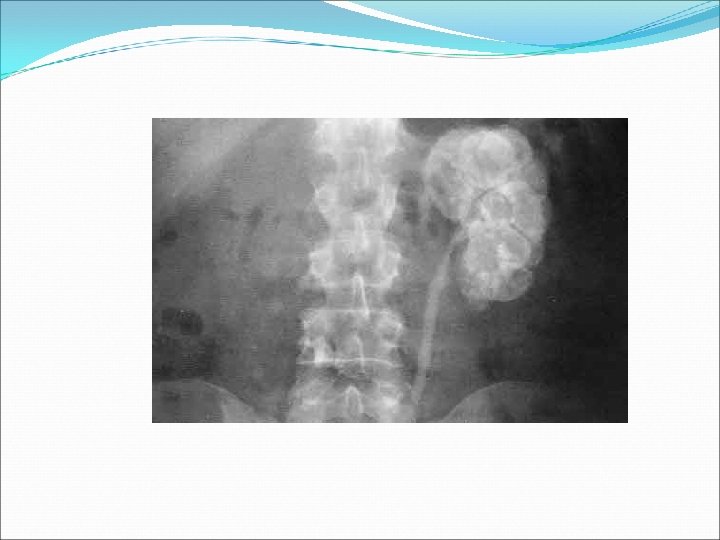

2. 3 Signes radiologique : le plus souvent l’atteinte est unilatérale • ASP retrouve : une lithiase, asymétrie de la taille des reins • UIV : signes de Pyélonéphrite chronique (PNC) : - petit rein asymétrique - contours irréguliers, encoches corticales - diminution de l’épaisseur du parenchyme rénale - déformation des tiges calicielles

UCR UIV : Reflux VU stade 4